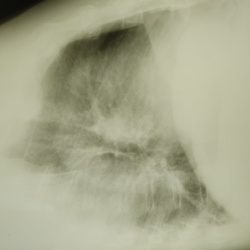

Здравствуйте, мужчина 64 года, неделю назад выставили левостороннюю нижнедолевую пневмонию. На данный момент клиника ушла. Прошлых снимков нет. В s9-10 это пневмо фиброз?

27.06.2024 - 23:04